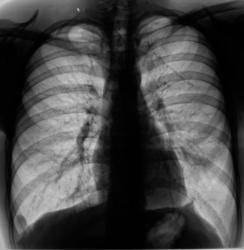

Произведена рентгенография в прямой и боковой проекциях.

Обнаружен "житель" в правом косто-диафрагмальном синусе.

Поставил за экран, и покрутил - следует за диафрагмой, в оптимальной проекции "на контур" выходит как "полусфера".